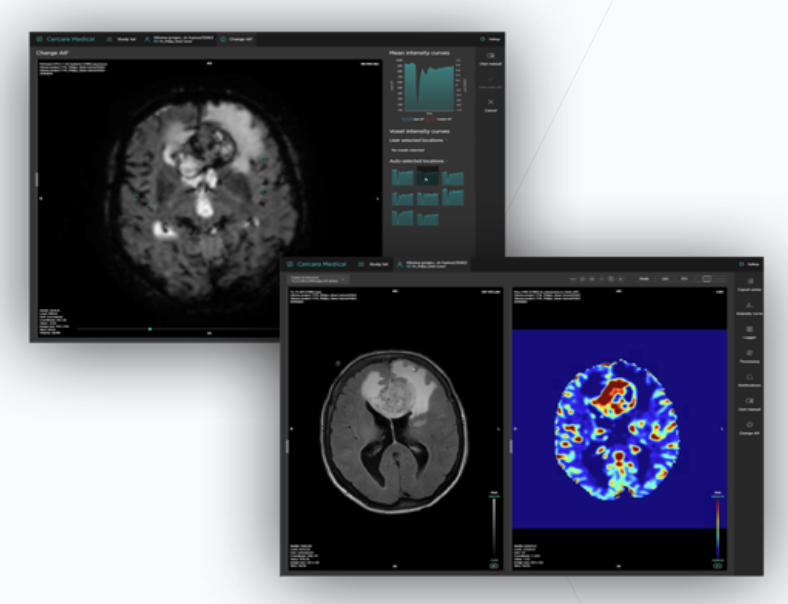

Cercare Medical Neurosuite

Cercare

A fully automated and multi-vendor compatible software solution for CT and MRI post-processing

Cercare MR Advanced

Fully automated and vendor-neutral perfusion processing application calculating high-quality perfusion maps